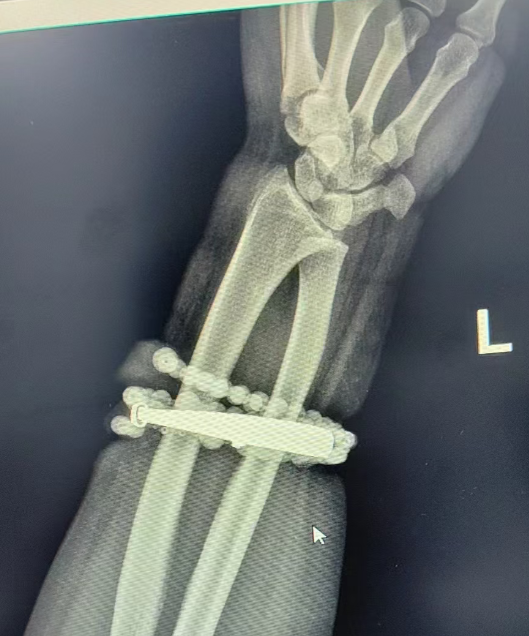

Sau khi nhập viện, bác sĩ xác định đây là trường hợp viêm mô mềm do vật thể kim loại chèn ép lâu ngày, kết hợp với nhiễm khuẩn, khiến mô thịt tăng sinh và "bọc" lấy vòng tay. Ca phẫu thuật kéo dài hơn một giờ đồng hồ. Các bác sĩ cẩn thận bóc tách và lấy ra cả vòng bạc lẫn chuỗi hạt, đồng thời tiến hành cắt lọc, làm sạch vết thương và dẫn lưu dịch mủ. Hiện sức khỏe của bệnh nhân đã ổn định, vết thương đang hồi phục tốt.